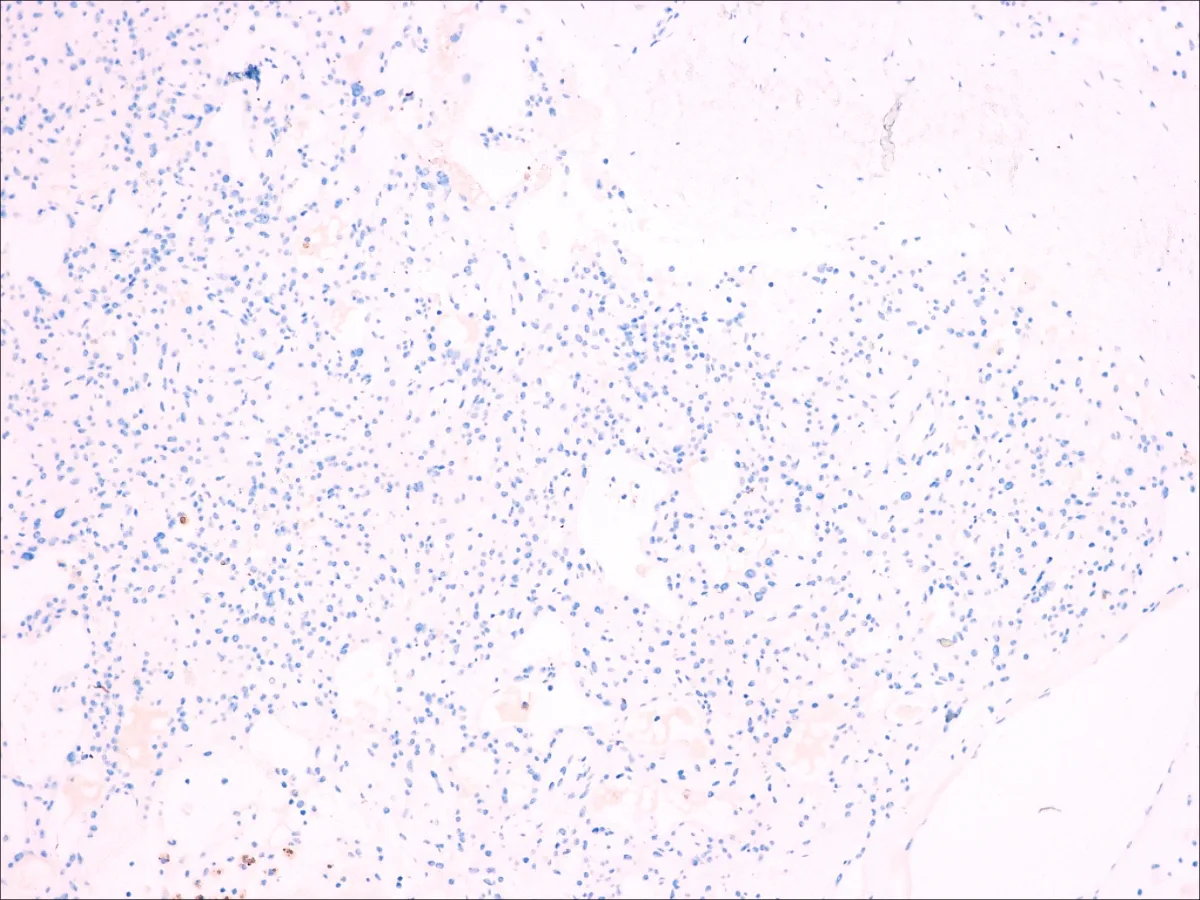

Diagnóstico: MESOTELIOMA EPITELIOIDE DIFUSO PERITONEAL

- Estos tumorales expresan Calretinina, Antimesotelio (HMBE1), Mesotelina, EMA, Trombomodulina, WT1, CK5/6, CK7, D2-40, Vimentina, Podoplanina y, en casos aislados, PAX-8 (PMID: 24183360).